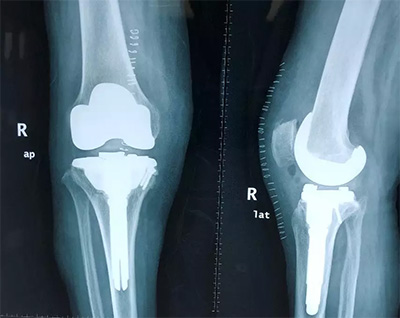

2、全膝關(guān)節(jié)置換

對(duì)于膝關(guān)節(jié)骨性關(guān)節(jié)炎終末期、類風(fēng)濕性關(guān)節(jié)炎、膝關(guān)節(jié)良性或惡性腫瘤的患者,如果膝關(guān)節(jié)疼痛、畸形,經(jīng)過(guò)保守治療無(wú)效,明顯影響生活質(zhì)量,則可行全膝關(guān)節(jié)置換手術(shù)。該手術(shù)可稱為膝關(guān)節(jié)置換術(shù)中的“補(bǔ)牙”技術(shù),應(yīng)用現(xiàn)代材料替代膝關(guān)節(jié)股骨、脛骨關(guān)節(jié)損壞的軟骨表面,從而減輕關(guān)節(jié)疼痛,恢復(fù)關(guān)節(jié)功能。